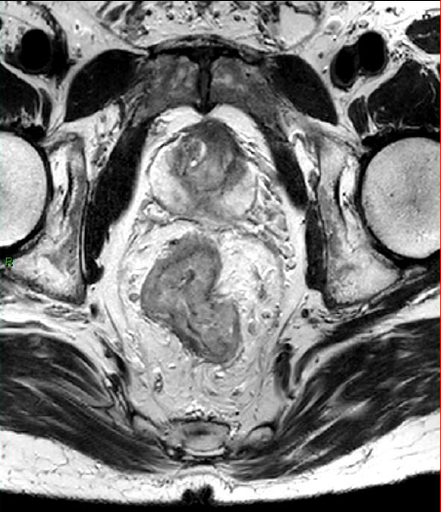

Pelvis : Caractérisation des masses annexielles de l'abdomen aigu à l'incidentalome

HOTTAT N. - ULB

Année académique 2021-2022

Imagerie de la femme DES SPECIALITE